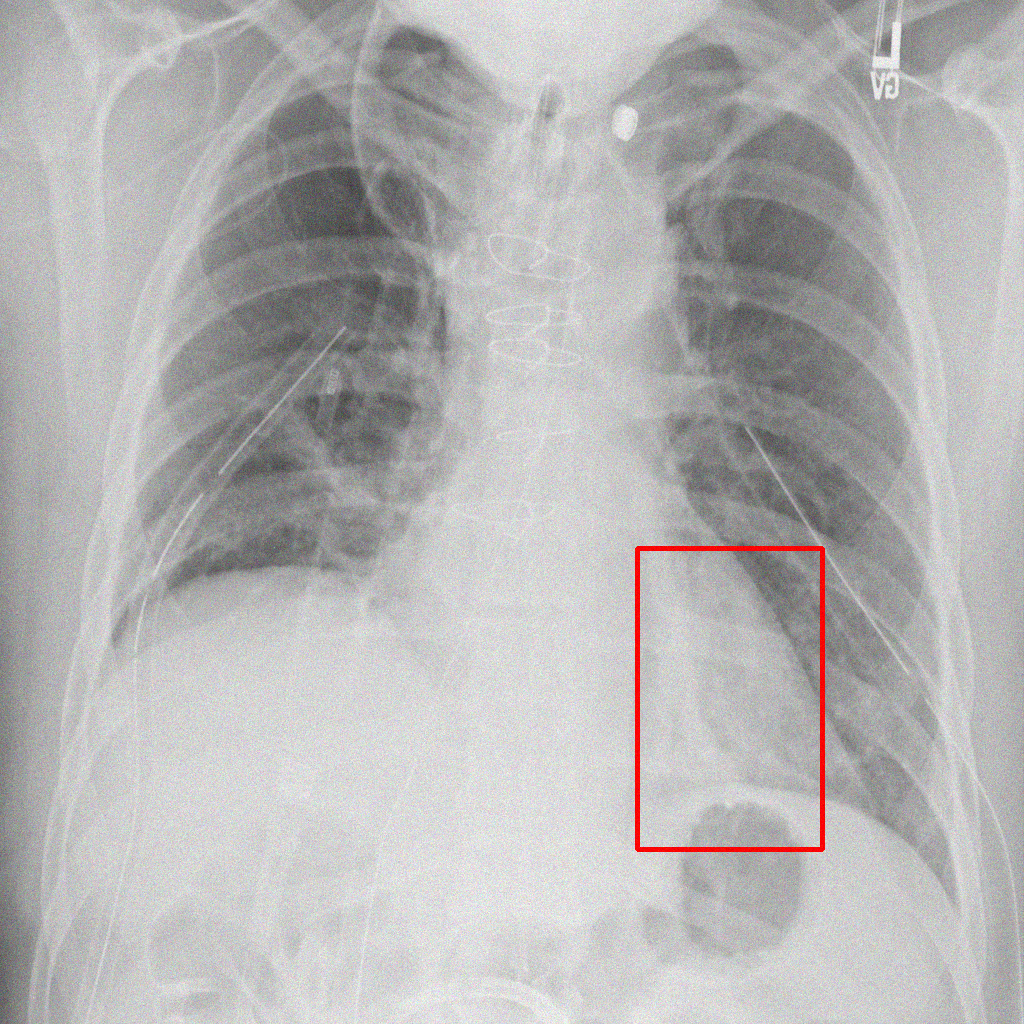

Object Rotation

X-ray GMAIMMbench Disease Diagnosis

Object Rotation - L1 (Moderate)

L1 (Moderate)

Question

Given the boxed region in the X-ray image, which abnormality is the image most indicative of?

A pneumothorax B pulmonary fibrosis C bone fracture D pleural effusion

Ground Truth: A. pneumothorax